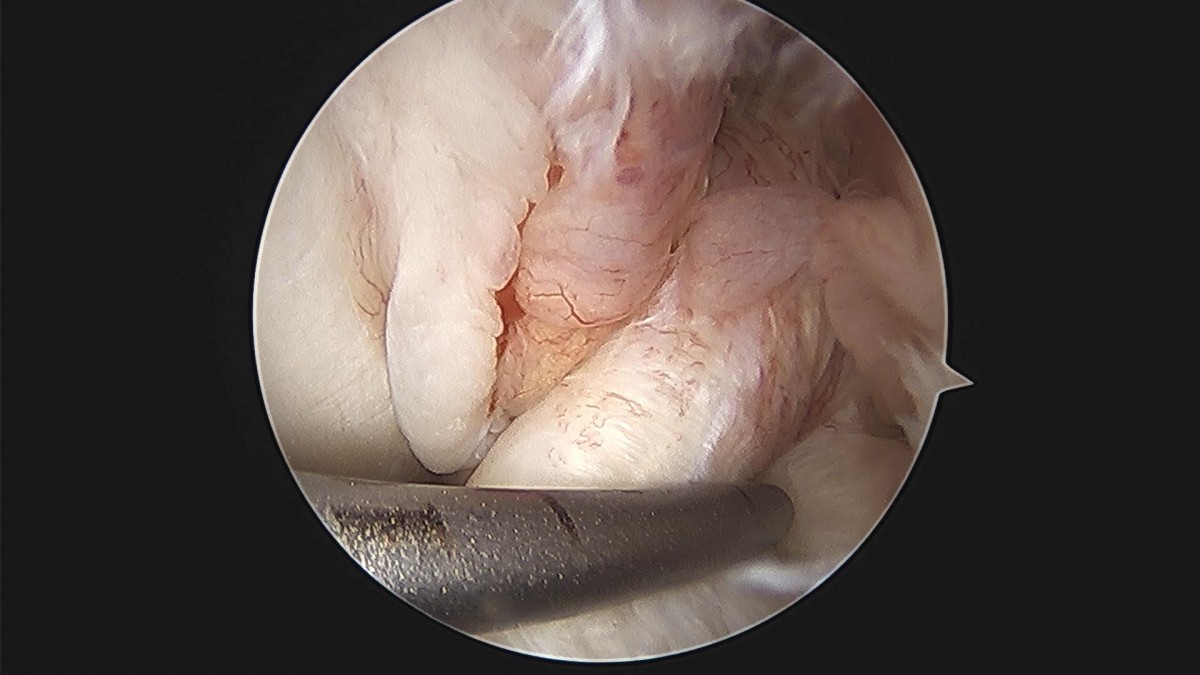

배우한 원장님 무릎 반월상 연골판 절제술 이순O 환자

작성자 최고관리자 댓글 0건 조회 1,744회 작성일 23-11-10 16:29